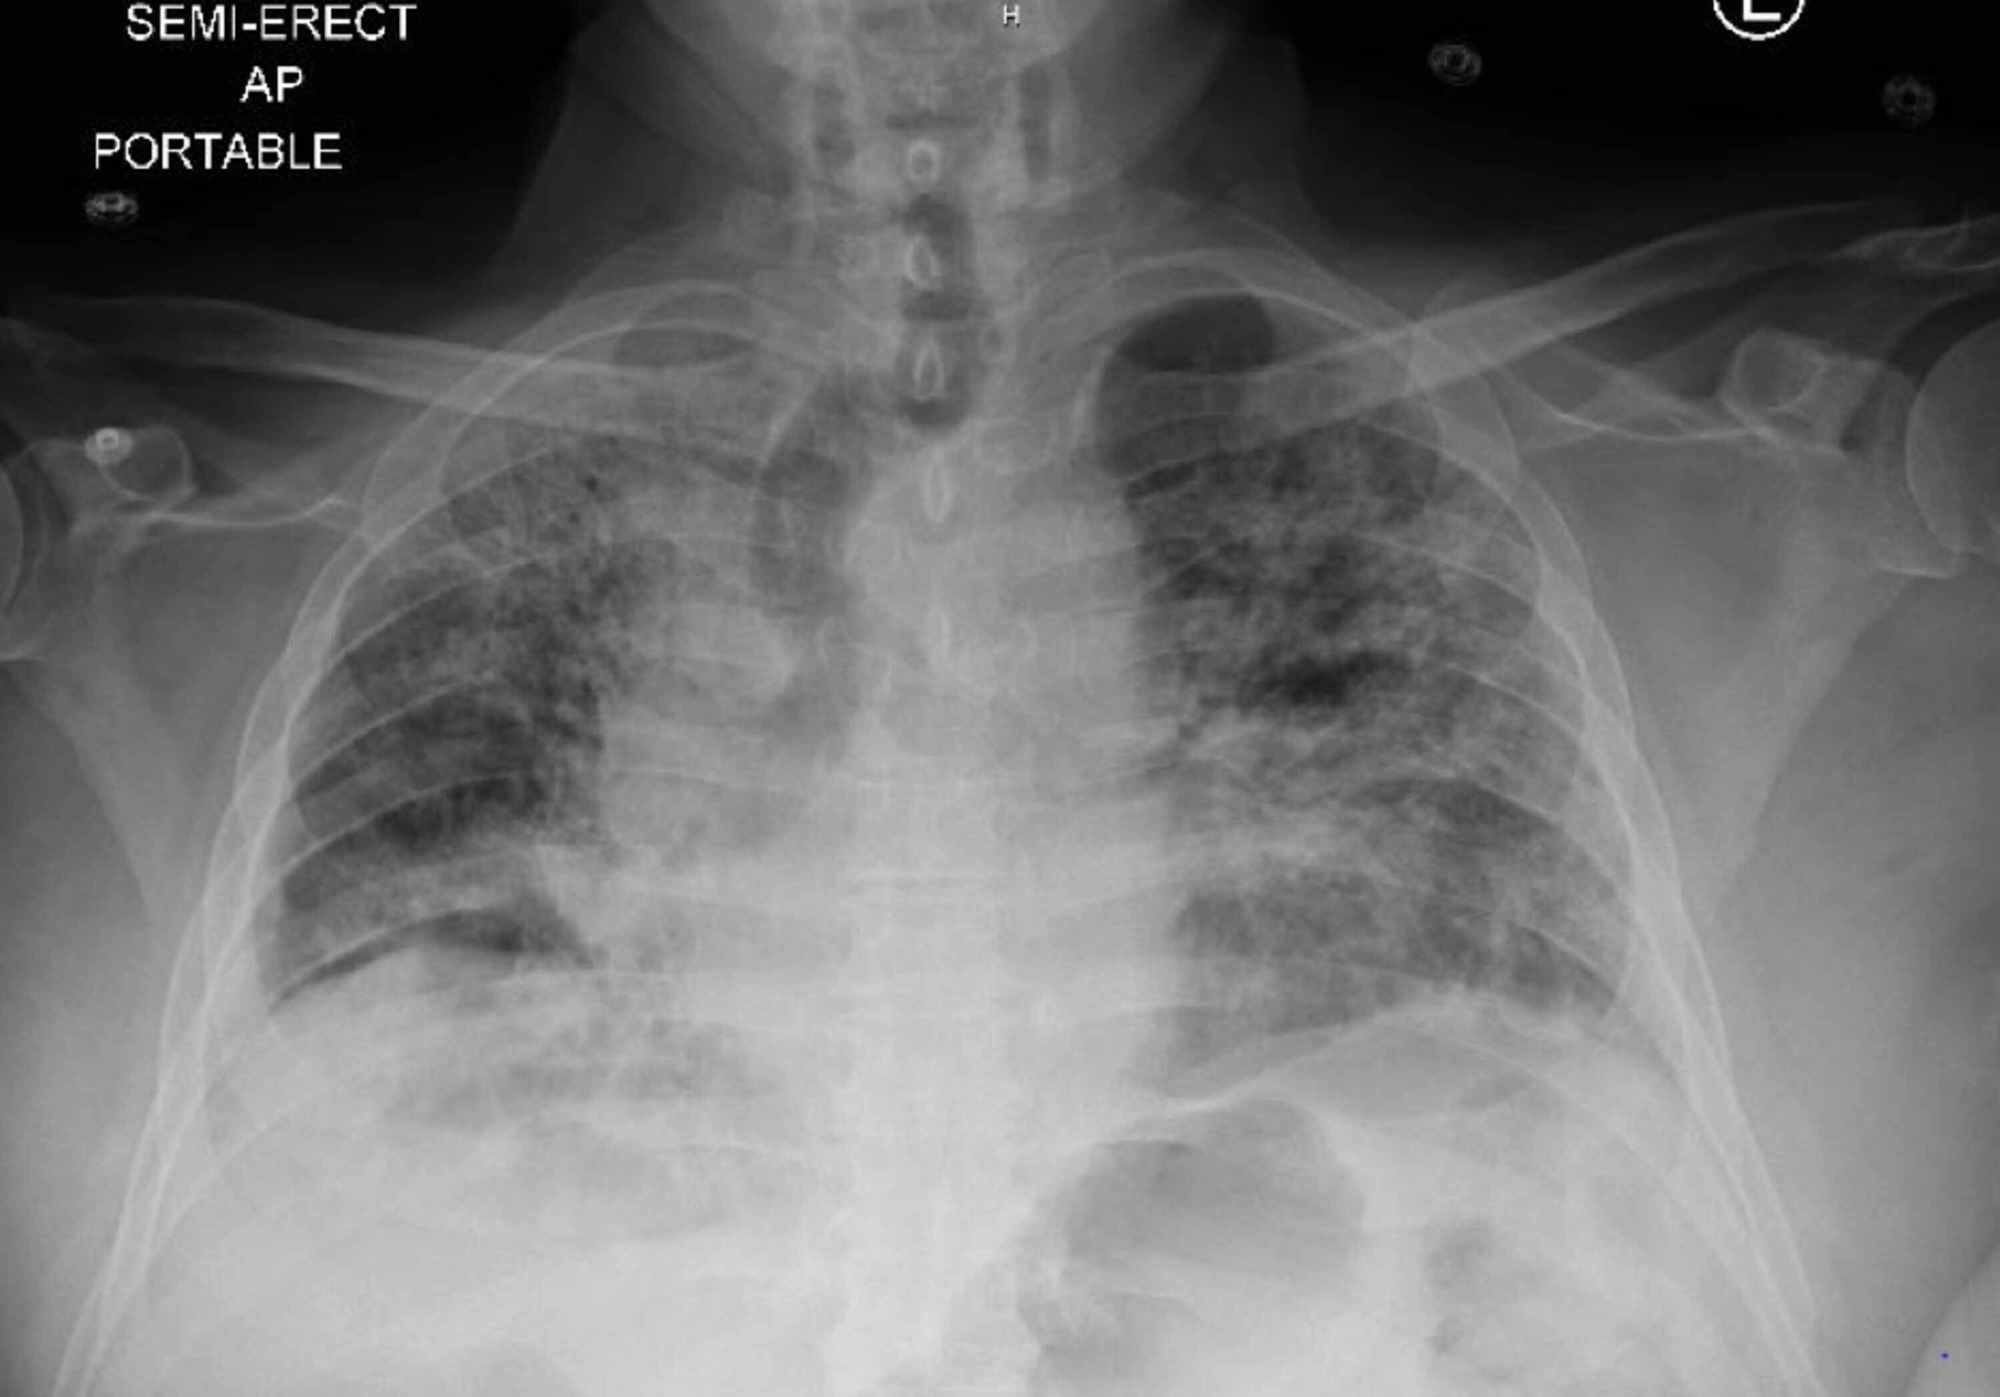

Bilateral Interstitial Infiltrates On Chest X Ray . An interstitial lung pattern is a regular descriptive term used when reporting a plain chest radiograph. Acute interstitial lung infiltrates seen on chest radiography are most commonly due to interstitial pulmonary edema or pneumonia. It is the result of the age. In the left middle lung periphery, an opaquer area of consolidation. While when used with a better anatomic reference, such as alveolar, air space, interstitial, or nodular, it may occasionally be helpful in suggesting an. Interstitial lung disease (ild) is an umbrella term that encompasses a large number of disorders that are characterized by diffuse. 12,13 however, virtually any form of.

Chest Xray shows bilateral lower lobe infiltrates consistent with Bilateral Interstitial Infiltrates On Chest X Ray Interstitial lung disease (ild) is an umbrella term that encompasses a large number of disorders that are characterized by diffuse. It is the result of the age. While when used with a better anatomic reference, such as alveolar, air space, interstitial, or nodular, it may occasionally be helpful in suggesting an. Acute interstitial lung infiltrates seen on chest radiography are. Bilateral Interstitial Infiltrates On Chest X Ray.

Initial chest Xray showing bilateral patchy infiltrates with lower Bilateral Interstitial Infiltrates On Chest X Ray It is the result of the age. While when used with a better anatomic reference, such as alveolar, air space, interstitial, or nodular, it may occasionally be helpful in suggesting an. Acute interstitial lung infiltrates seen on chest radiography are most commonly due to interstitial pulmonary edema or pneumonia. 12,13 however, virtually any form of. In the left middle lung. Bilateral Interstitial Infiltrates On Chest X Ray.